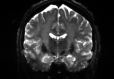

Refer to captionRefer to captionRefer to captioninitializationOptimal TransportRefer to captionRefer to captionRefer to captionOptimal Transport (blurred)Refer to captionRefer to captionRefer to captionMultilevelRefer to captionRefer to captionRefer to captionoptimizedRefer to captionRefer to captionRefer to captionRefer to captionRefer to captionRefer to caption

Figure 6: Example field maps (Subject ID 826353) at initialization (top row) and after optimization with Gauss-Newton (bottom row). The first column uses the proposed optimal transport initialization scheme. The middle column uses the same scheme with an additional Gaussian blur to promote smoothness. The right column uses the coarse-to-fine multilevel initialization scheme from HySCO with five levels, and the final field map is optimized at the original image resolution. The multilevel initialized field map is smooth by construction and further optimized to improve the relative image distance at the full resolution. The optimal transport initialization accurately corrects the distortions but is not smooth in the non-distortion dimensions unless blurred with a Gaussian. After the fine-level optimization all field maps are visually similar.